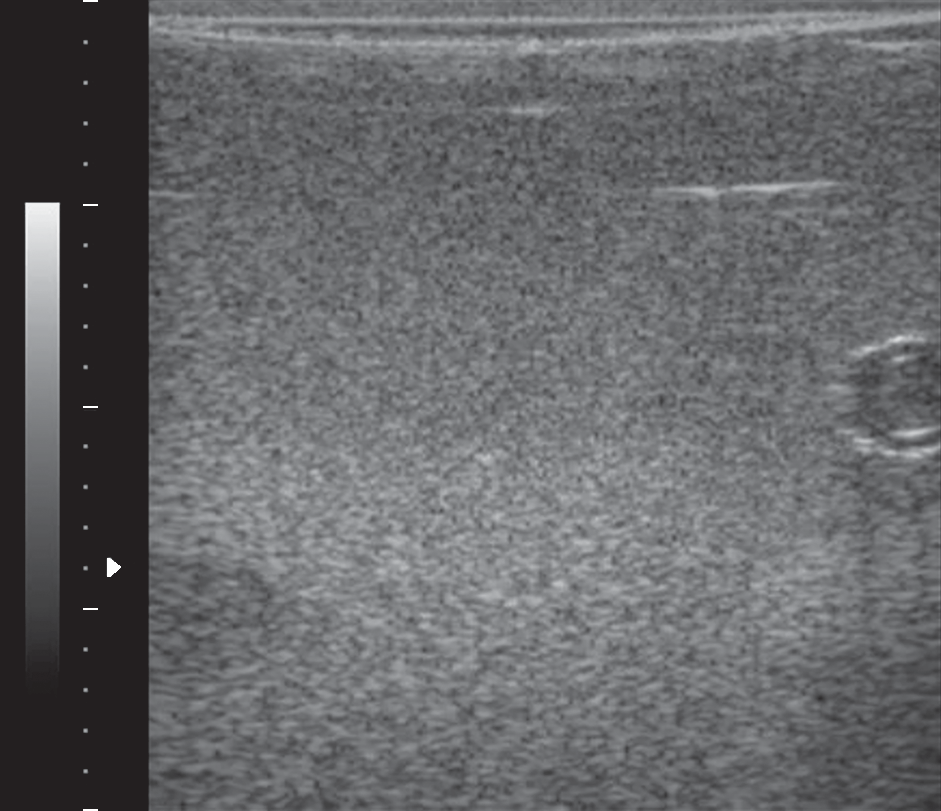

The paper considers a fundamentally new approach to solving the problem of determining the size of structural formations in ultrasonic diagnostics, based on the theoretically justified possibility of estimating the size of inhomogeneities of the studied medium by analyzing the statistical characteristics of the ultrasonic signal scattered on these inhomogeneities. This possibility is conditioned by the fact that the statistical distribution of the ultrasound image data varies from Rayleigh distribution to Reiss distribution depending on the relation between the coherence area size of the scattered signal and the beamwidth. The work aims at the development of a new method of statistical data analysis, which will effectively detect a significant coherent component in the echo signal and thereby be used as a mathematical tool to estimate the size of medium inhomogeneities in ultrasound imaging. Such approach to the analysis of ultrasound images would provide a possibility of quantitative estimation of structural formations and thereby would increase significantly the information value of ultrasound diagnostics and possibility of pathology detection at early stages of its formation that opens perspectives for treatment efficiency increase.